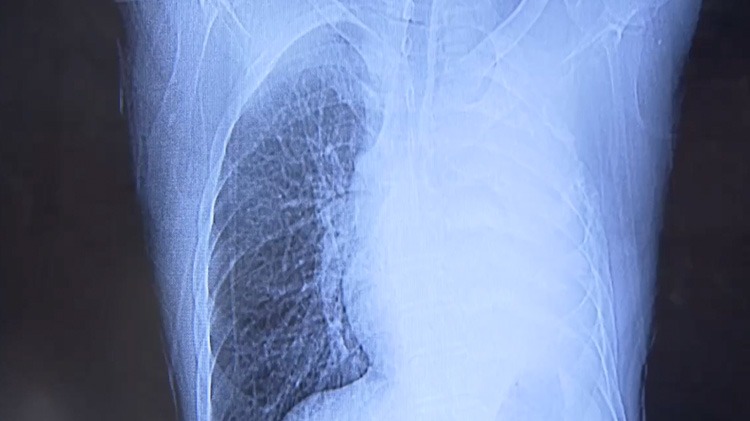

根据国家癌症中心最新数据统计显示,2022年我国癌症新发病例中,肺癌占比22%,位居第一;癌症患者死亡人数中,肺癌占比28.5%,也位居第一。肺癌已然成为我国发病率及死亡率最高的恶性肿瘤,应当引起大众关注。而在临床上,肺癌患者所处的病情阶段不同,其治疗方案和预后情况也有所不同。为此,今天我们请来了上海交通大学医学院附属胸科医院的两位专家,他们是肿瘤科主任李子明教授和肿瘤科副主任成兴华教授,成教授同时也主持外科工作。两位教授将从外科和内科不同专业角度,为大家介绍肺癌从早期到晚期的诊疗创新方式。